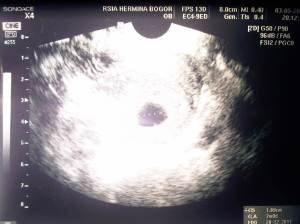

Cek pertama, taunya sudah 7 minggu, sudah kelihatan pertumbuhannya